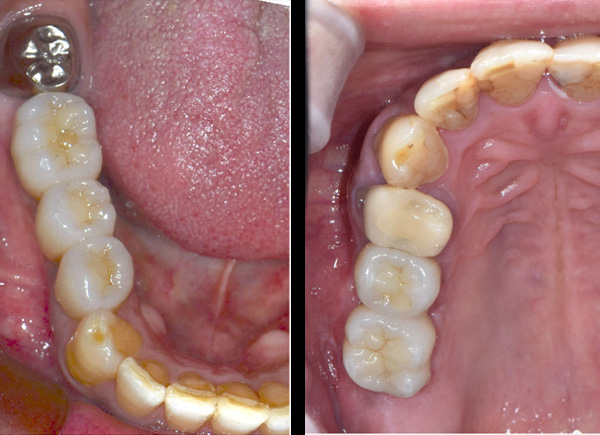

| 年代・性別 | 50代 男性 |

|---|---|

| 主訴 | 右下の歯がないのでインプラントをして欲しい |

| 治療期間 | 約6ヶ月 |

| 費用 | 600,000円 |

| 治療内容 | インプラント、骨造成、結合組織移植、セラミック修復 |

| 治療に伴うリスク | インプラント周囲炎 セラミックの破折、脱離 |

*キャンセルポリシーをご一読のうえご予約ください